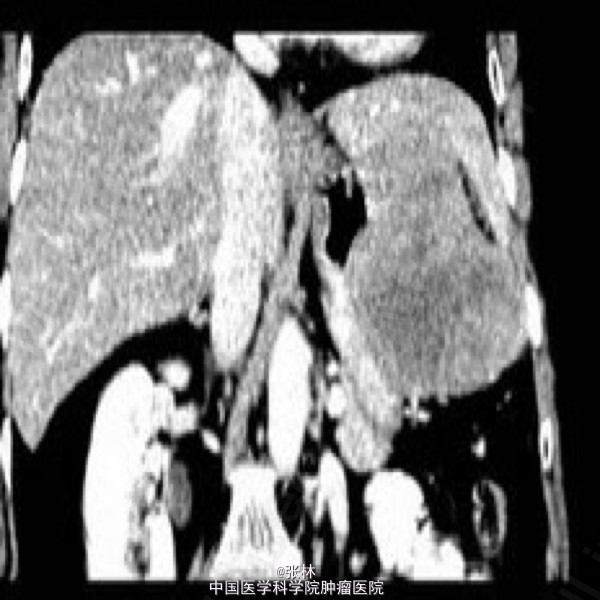

病史:女,65岁,上腹不适3年。

CT表现:胃体部前外侧壁可见一外生性肿物,体积大,形态较规则,边界清楚,肿物与邻近胃壁不可分,胃腔受压变扁;平扫呈较均匀等或略低密度,增强扫描明显不均匀强化,周边实性部分呈渐进性强化,中心可见片状无明显强化的更低密度区域。

术中:肿物位于胃前壁体底交界处,约12X10X10cm,占据上腹大部分,于肝左外侧叶稍粘连,肿物呈暗红色,质硬,肿物附近胃壁颜色、质地正常。 病理诊断:胃高度恶性间质瘤。